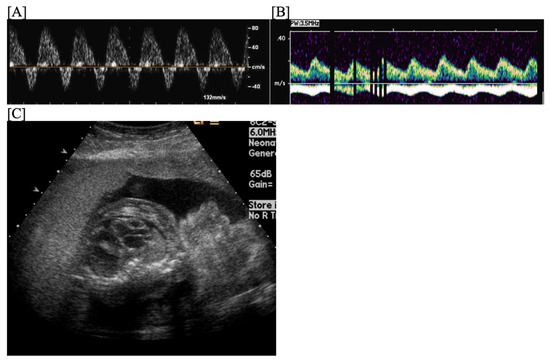

- Fouron, J.C.; Proulx, F.; Miró, J.; Gosselin, J. Doppler and M-Mode Ultrasonography to Time Fetal Atrial and Ventricular Contractions. Obstet. Gynecol. 2000, 96, 732–736. [Google Scholar] [CrossRef] [PubMed]

- Carvalho, J.S.; Prefumo, F.; Ciardelli, V.; Sairam, S.; Bhide, A.; Shinebourne, E.A. Evaluation of Fetal Arrhythmias from Simultaneous Pulsed Wave Doppler in Pulmonary Artery and Vein. Heart 2007, 93, 1448–1453. [Google Scholar] [CrossRef] [PubMed]

- Howley, L.W.; Schuchardt, E.; Park, D.; Gilbert, L.; Gruenwald, J.; Cuneo, B.F. Simultaneous Recording of Pulsed-Wave Doppler Signals in Innominate Vein and Transverse Aortic Arch: New Technique to Evaluate Atrioventricular Conduction and Fetal Heart Rhythm. Ultrasound Obstet. Gynecol. 2018, 52, 544–545. [Google Scholar] [CrossRef] [PubMed]

- Detterich, J.A.; Pruetz, J.; Sklansky, M.S. Color M-Mode Sonography for Evaluation of Fetal Arrhythmias. J. Ultrasound Med. 2012, 31, 1681–1688. [Google Scholar] [CrossRef] [PubMed]